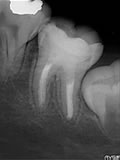

根管治療とは歯の根っこの治療のことで、歯の神経が入っている管を治すために行う処置、または歯の根の先の膿袋の治療を行うことをいいます。